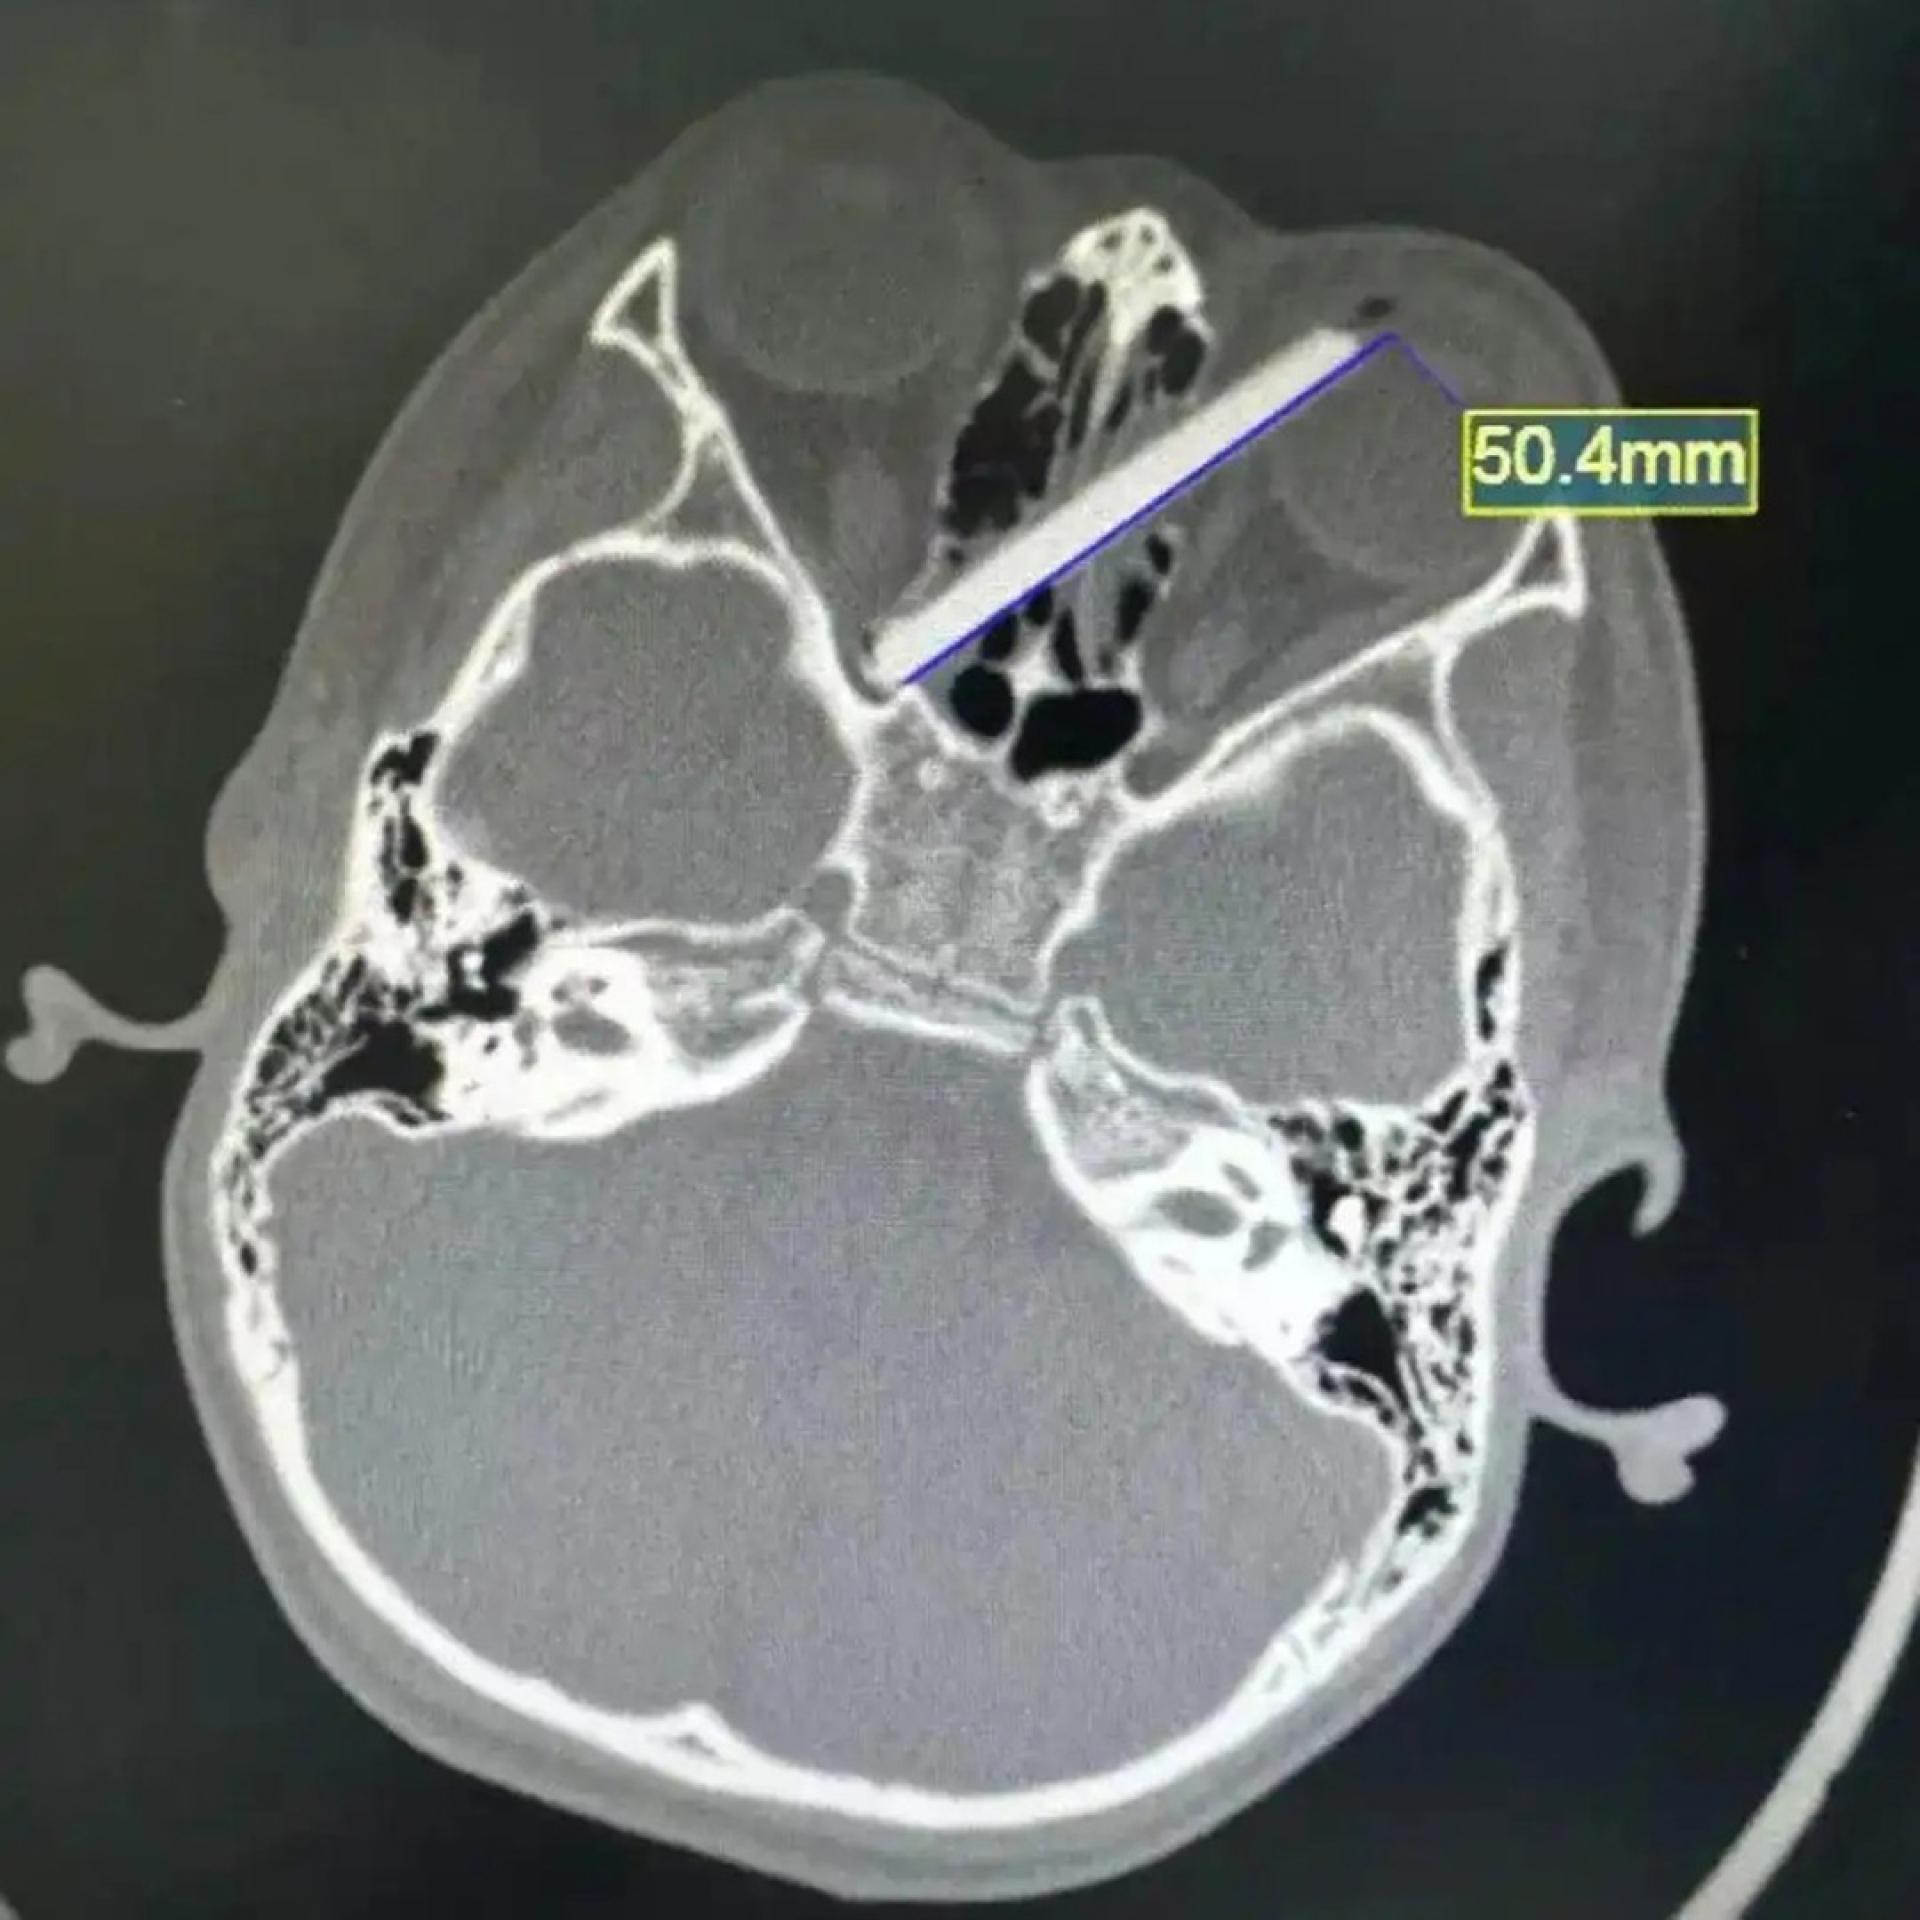

男童家长心急如焚地表示,事发时孩子拿著筷子准备开饭,突然摔了一跤,手中的筷子便少了一截,他们遍寻不获,猜测断筷已插入儿子眼中。经电脑扫描(CT)检查后,证实了家长的猜测。影像显示,该截5厘米长的断筷,由左眼球壁插入,横向贯穿双侧鼻窦,其尖端更深嵌至右眼的视神经管附近。